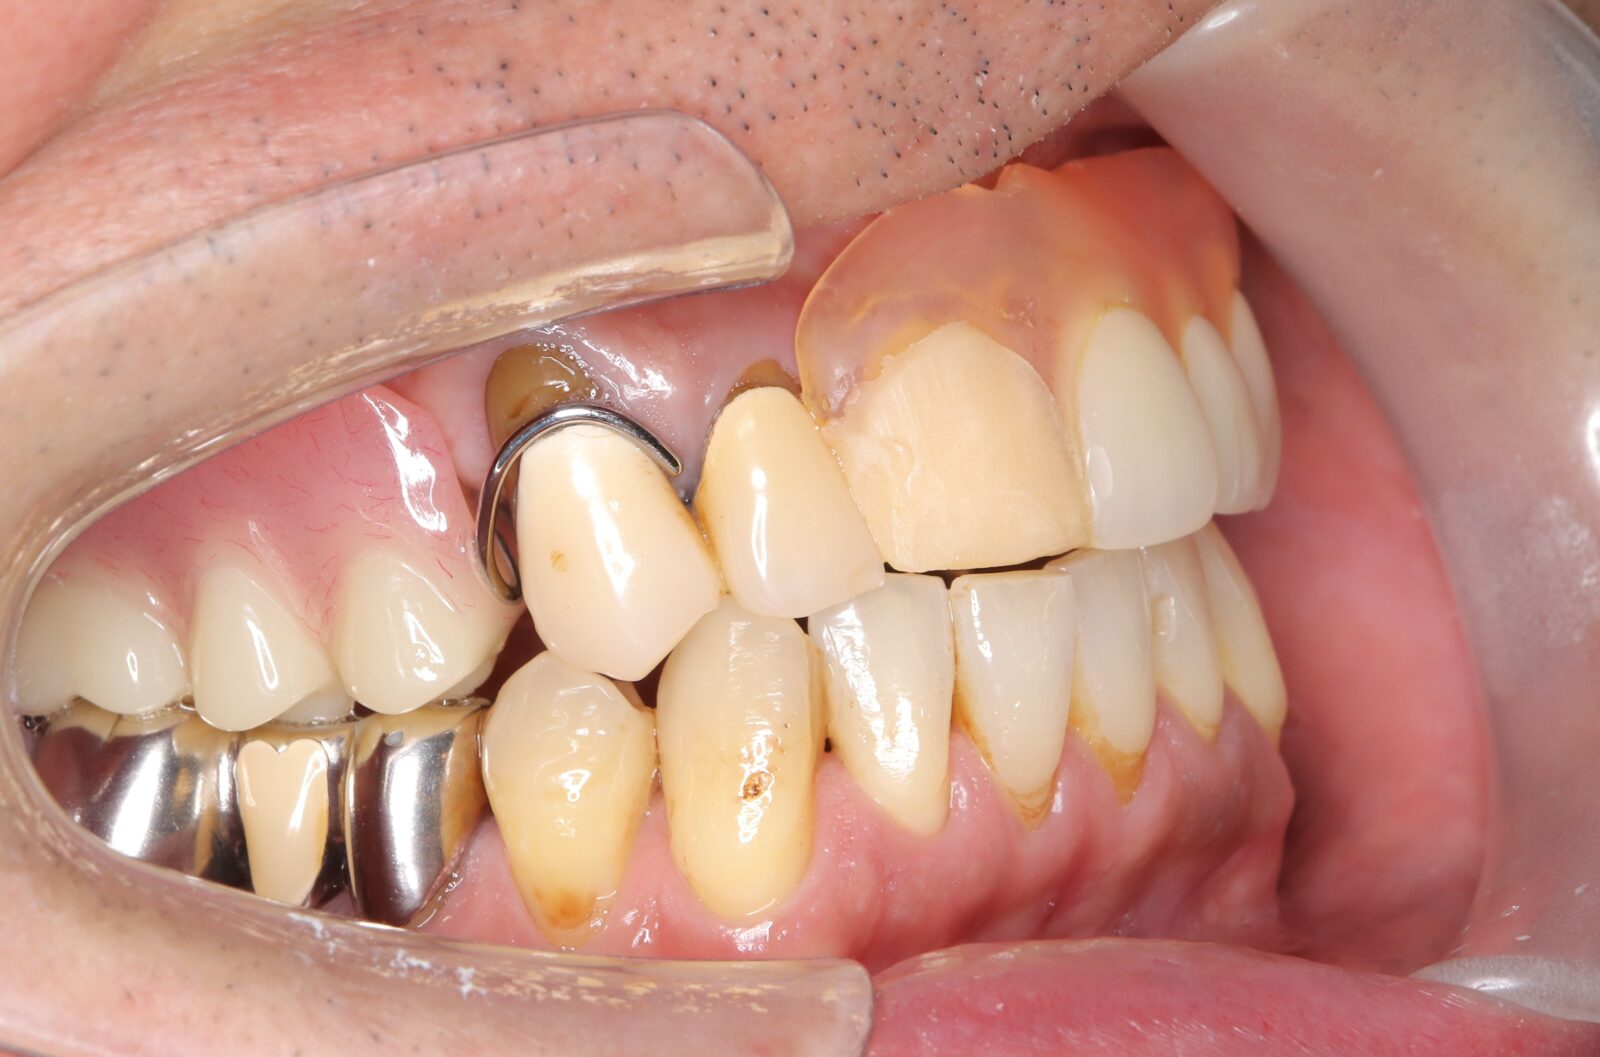

矯正と補綴が必要で実施した症例

左側に隙間。歯の数が少ない。もともと2番と7番がない。(先天欠如)歯の数が少ないため上顎のアーチ全体が小さい。歯槽骨の幅も狭く、歯肉も薄い。骨質も弱かった。

上顎左右2番と6番が先天欠如。下顎左右1番も先天欠如でもともとブリッジが装着されていた。

左右非対称なすきっ歯。上顎の前歯がないので左側の隙間を左右2番相当部に集めた。

上下の前歯が反対の噛み合わせ(受け口)で、干渉しているためうまく閉じることができず、奥歯は左右同時に噛めないので、どこかにずらさないと口を閉じられない。

左右の歯を同時に合わせることができず、どこで噛んだら良いかわからない噛み合わせでした。

小臼歯部は噛み合うことがない側方の開口状態。矯正と補綴が必要なケース。 主訴は顎の不調と歯軋り、夜間の食いしばり。

マルチブラケットとインビザラインを併用し、クラウンとブリッジを装着しました。

上顎左右2番は、歯が入るスペースを作り、ブリッジを装着しました。

他の歯医者で何軒も断られていました。 骨の幅がうすくインプラントはできない。骨の質も柔らかい。PCR検査の結果も歯周病ハイリスク患者でした。

歯の位置は、本人の顎が安定する場所を探して着地した。 左右で噛み合わせが非対称で、理想的な歯のポジションを獲得できなかったものの、左右同時に噛むことができるようになった。

顎関節の症状も落ち着いて、開口障害や、顎の痛みは無くなった。

矯正治療はどの装置を選択しても歯周病のリスクを高めてしまう。

これ以上の歯の移動が歯周病と骨質、骨の代謝のバランスの兼ね合いで困難であると判断し、ここが着地点とした。